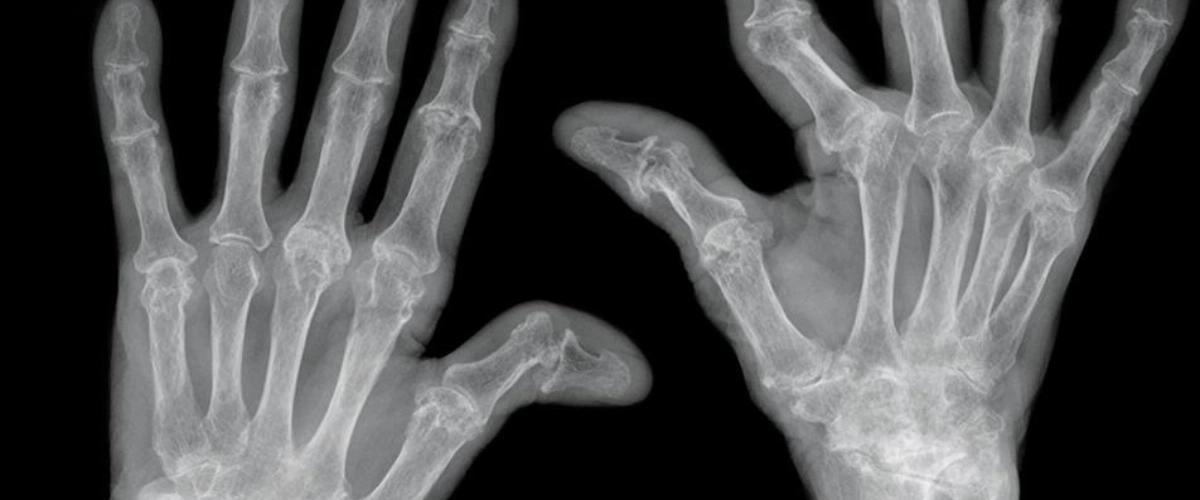

Для разработки новой диагностической технологии ученые исследователи синовиальную жидкость, содержащуюся в суставах. Главным образом изучались метаболические различия в здоровых и поврежденных суставах. Специальный метод визуализации в сочетании с искусственным интеллектом отслеживали мельчайшие индикаторы, связанные с артритом. В результате был разработан датчик, который по образцу синовиальной жидкости выявлял артрит за 10 минут, пишет EurekAlert.

Исследование с участием 120 пациентов показали, что новая технология с точностью 94% выявляет остеоартрит и ревматоидный артрит, а с точностью 95% определяет тяжесть прогрессирования обоих заболеваний.